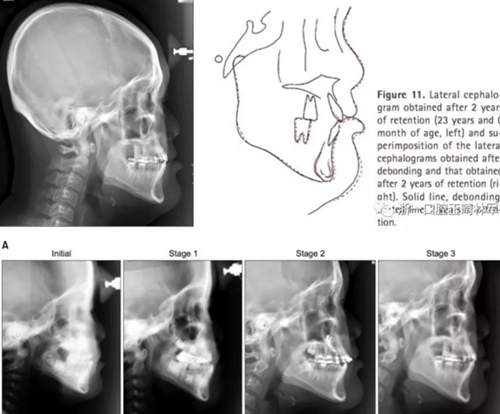

頭側(cè)結(jié)果顯示上頜輕度后縮(SNA 79.1°; A to N,-5.0mm;A到VRP水平距離為57.5mm),下頜輕度前突(SNB,80.2°,Pog-N-7.2mm;POG到VRP水平距離,57.4mm),低角ANB(-1.1°),正常下頜平面角(FMA,29.5°),正常下頜角(119.8°),上頜切牙斜度正常(U2 to SN,106.7°)和下頜切牙的舌傾角(IMPA,85.0°)。正常的覆合和覆蓋(覆合,1.7mm,覆蓋,1.9mm)(圖8和9,表3)。

2年后隨訪提示治療結(jié)果得到保持(圖10,11,表1-3),不同階段的頭側(cè)重疊結(jié)果見圖12。